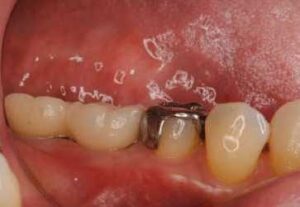

今日もインプラントの症例です。 奥歯の噛み合わせが無いインプラント症例の方の治療がほぼ終了しました。 二年ほど前から治療していました。奥歯が無いので、前歯も少しグラグラしてきてインプラントを希望されました。 やはり、早く奥歯の噛み合わせが安 […] 本文を読む